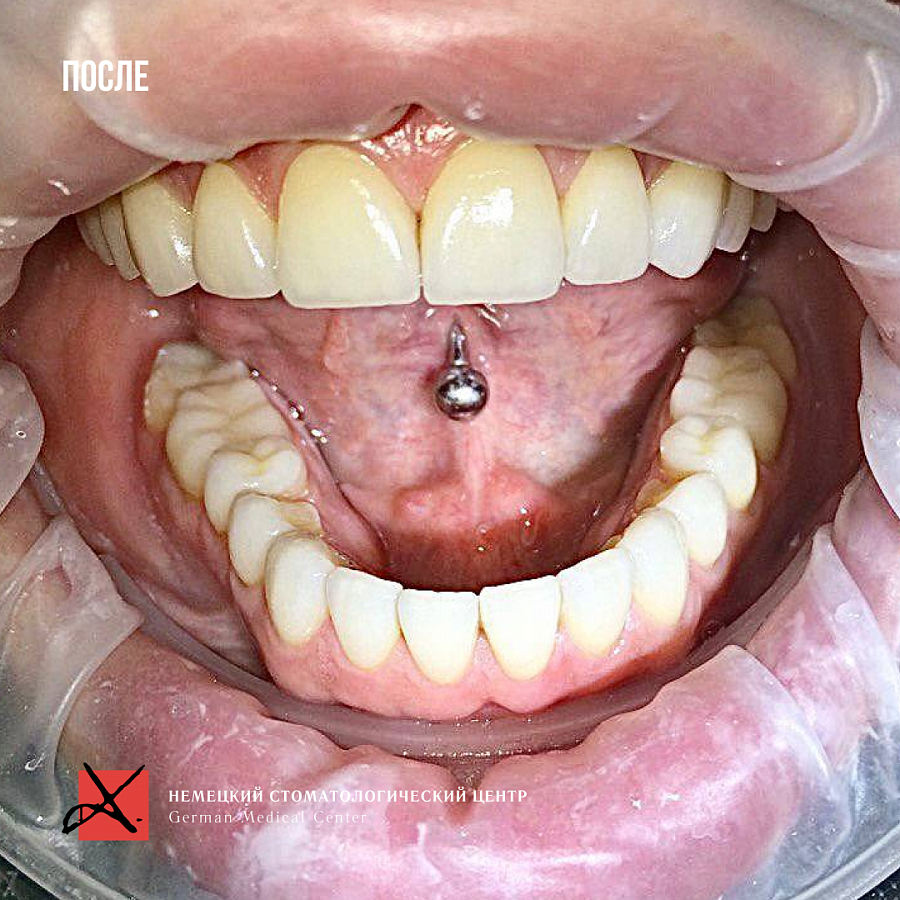

- выраженная стираемость зубов

- поврежден край переднего зуба семечками

В первую очередь был запрос на эстетическую часть. Пациентка хотела, чтобы новые зубы выглядели естественно.

Провели санацию, сделали и установили красивые натуральные виниры.

Результат на фото говорит лучше всяких слов. Пациентка очень довольна результатом!